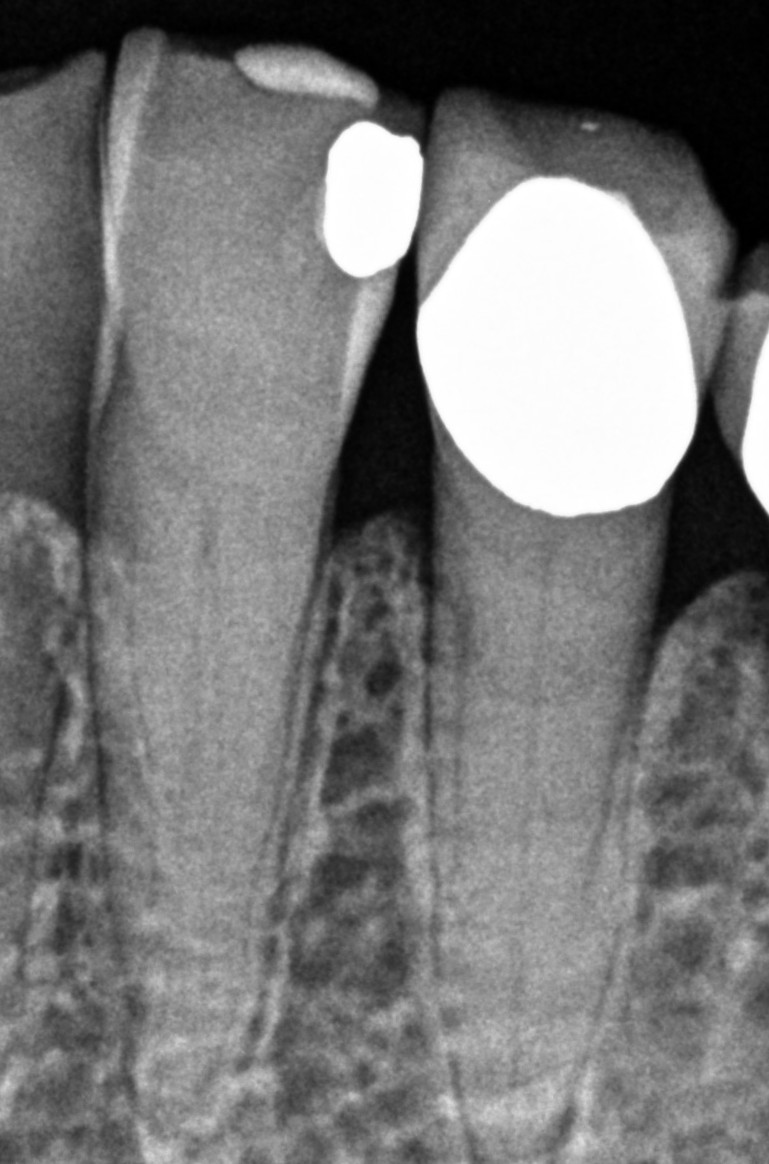

See My Work

Cases